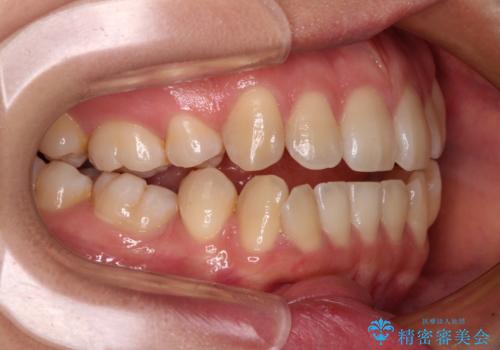

- 上下顎前歯部の非接触(開咬)と下顎のデコボコを主訴に来院された患者様です。

右側上下と左上の小臼歯が一本ずつ少なく、さらに骨格的な左右差もあり上下の真ん中の位置がずれています。

下顎のデコボコの解消と、真ん中の位置を改善するために左下の小臼歯を抜歯することとしました。

また、開咬を改善するため臼歯部にアンカースクリューを用いて圧下する力をかけていきました。